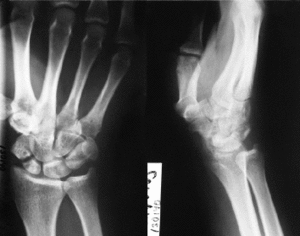

El tratamiento actual de las lesiones óseas del carpo se realiza teniendo en cuenta las estructuras ligamentosas que sostienen a este sistema,9-12reconociéndose que es la estabilidad del carpo el parámetro que va a decidir e interferir en la evolución de una lesión carpiana.8-15,20 Según estos principios, en el tratamiento de la pseudoartrosis del escafoides carpiano se considera esencial la consecución de una adecuada reducción anatómica tanto en longitud como en morfología, desviaciones angulares y desplazamiento lateral, restableciendo la estabilidad intrínseca del carpo. Según Fisk11 y Fernández8-10 puede establecerse una diferenciación entre dos tipos de pseudoartrosis: las pseudoartrosis estables, no desplazadas o sin deformidad, y las inestables, desplazadas o anguladas. Las segundas suelen presentar una deformidad radiológica típica conocida como DISI y una imagen radiológica del escafoides en proyección lateral conocida como humpback deformity (traslación volar, flexión, desviación cubital y pronación). Esta diferenciación tiene importancia tanto pronóstica como terapéutica y así sugieren que sólo es aplicable la técnica clásica de Russe en los casos de pseudoartrosis sin deformidad en flexión del escafoides, acortamiento o inestabilidad carpiana asociada, o colapso. Para el resto de situaciones el injerto triangular o trapezoidal es el idóneo para restablecer las deformidades en flexión en el plano sagital y la angulación radial deseada en el plano frontal, así como para corregir la longitud del mismo. También es importante realizar la intervención lo más precozmente posible, pues a medida que la pseudoartrosis evoluciona las alteraciones anatómicas, óseas y funcionales se incrementan y se estructuran, haciendo más difícil el restablecimiento de la congruencia articular y ligamentosa del carpo. De hecho, en la presente serie los pacientes con más alteraciones radiológicas y con artrosis carpiana incipiente, que posteriormente en las revisiones no han mejorado a pesar de la consolidación de la fractura, son aquellos en los que la inestabilidad del carpo no se ha corregido y la artrosis carpiana ha continuado desarrollándose; sin embargo, el hecho de no haber encontrado relación entre la presencia de dolor y la artrosis del carpo puede deberse al corto período de seguimiento del estudio. Así se ha observado que un buen resultado anatómico y funcional no se va a deteriorar ya con el paso del tiempo y va a permitir prevenir las secuelas tardías de artosis (Fig. 1); por otro lado, la consolidación ósea sola no es suficiente per se para la curación y desaparición del dolor.

A

BC

DFigura 1. A y B: Pseudoartrosis de 13 meses de evolución desde el traumatismo conocido con dolor de muñeca moderado. C: Tras la intervención se objetivó consolidación radiológica definitiva a las 20 semanas de evolución postoperatoria, con un ángulo escafolunar normal y un resultado funcional bueno. D: A los 3 años de evolución postoperatoria se objetiva el mantenimiento del resultado radiológico y mejoría del resultado funcional con vuelta a la actividad laboral previa.